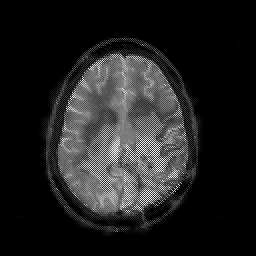

Glioblastoma multiforme overlay -- Slice #37

[Home][Help][Clinical][Tour 1][Tour 2][Tour 3] Slice 37